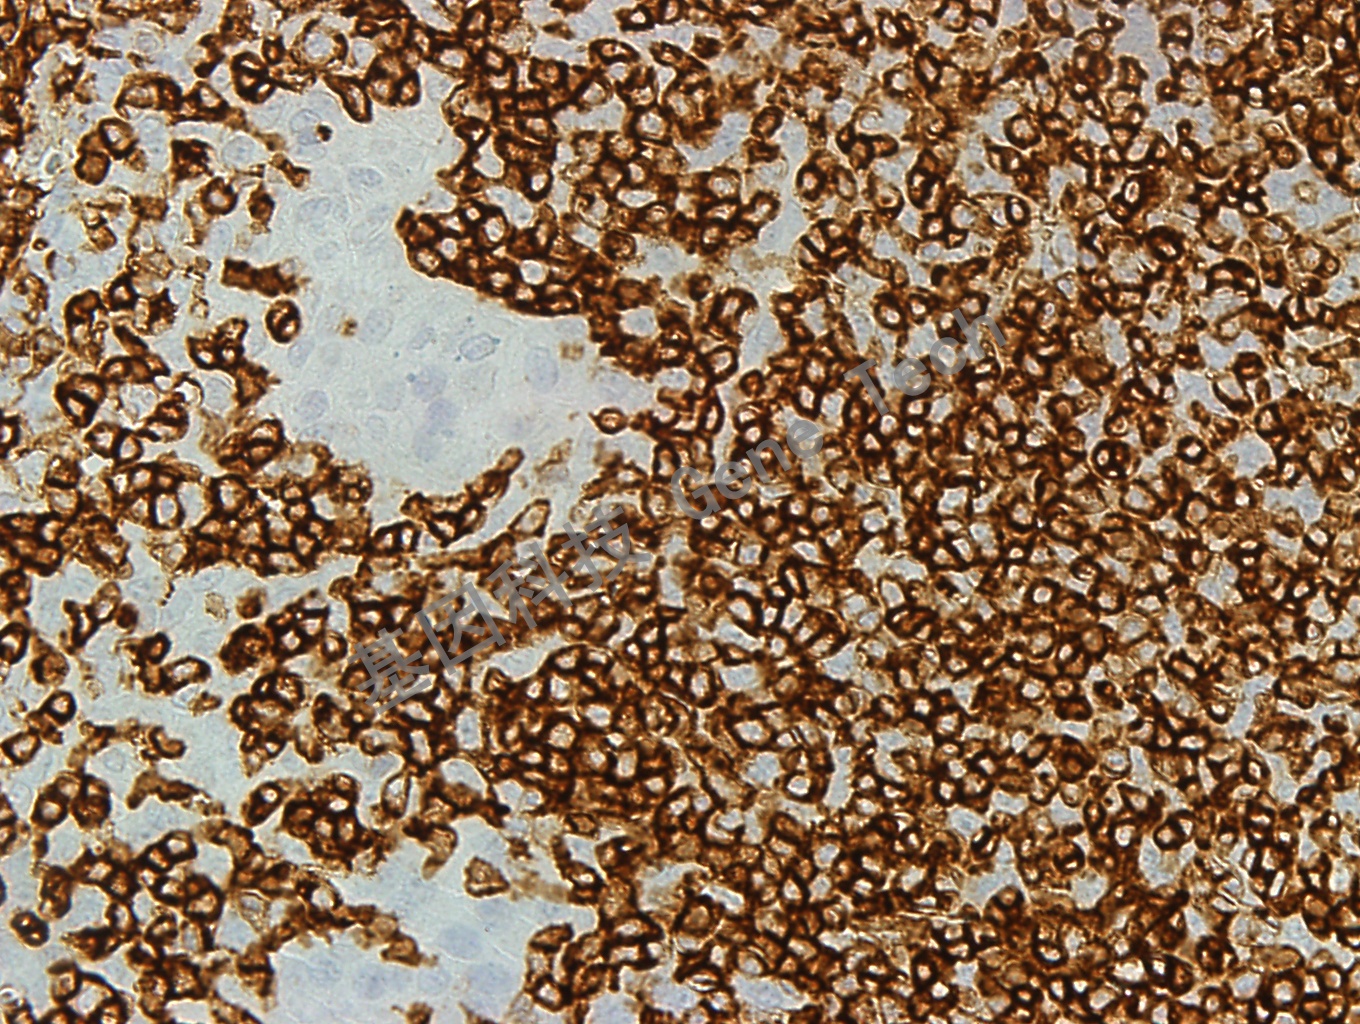

| 扁桃體石蠟切片,用 CD45RB(GT2219)染色,細(xì)胞膜陽性,DAB 顯色。(40X) | ||

| 克隆號(hào):PD7/26 | 陽性對照:扁桃體 | 陽性部位:細(xì)胞膜 |

| 預(yù)處理:高pH熱修復(fù) | 適用:石蠟切片/冰凍切片 | 顯色系統(tǒng):GTvisionTM |